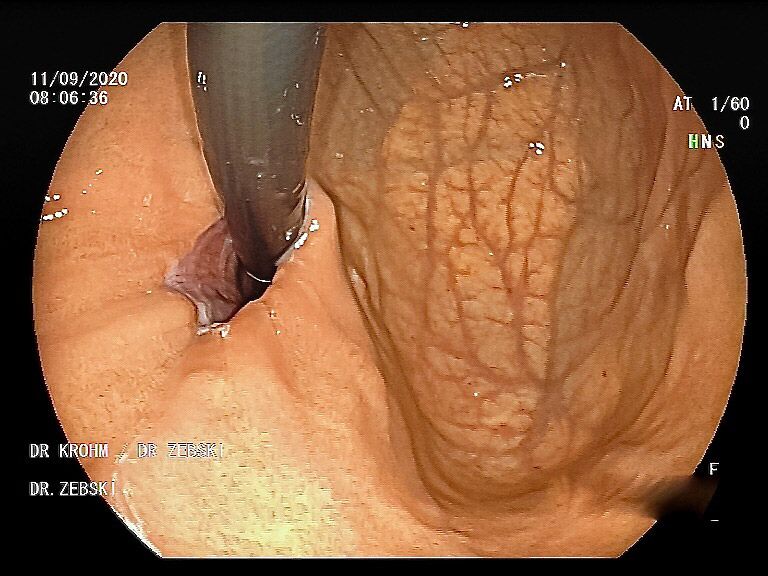

Mit einer Gastroskopie werden Speiseröhre, Magen und Zwölfingerdarm (der oberste Teil des Dünndarms) untersucht. Dazu wird ein geschmeidig biegsames, schlankes Endoskop mit eingebauter Digitalkamera durch den Mund eingeführt. Minimalste Veränderungen können dabei gesehen werden, die im Röntgenbild oder einer Kernspintomographie (MRT) noch gar nicht erkannt werden. Im Vergleich zu anderen bildgebenden Untersuchungsverfahren ist bei der Endoskopie neben der wichtigen optischen Beurteilung auch die sofortige Möglichkeit gegeben, Gewebeproben aus auffälligen Bereichen zu entnehmen. Dazu wird eine kleine Spezialzange durch einen Kanal im Endoskop geschoben und die Probe ganz präzise aus dem entsprechenden Gewebe gewonnen. Da die Schleimhäute schmerzunempfindlich sind, spüren Sie davon nichts. Die Proben werden von Spezialisten mikroskopisch untersucht und ermöglichen dann eine zielgerichtete Therapie; zum Beispiel wenn eine Magenschleimhautentzündung durch eine chronische Infektion ausgelöst wird, die mit einer Antibiotikakur erfolgreich behandelt werden kann.